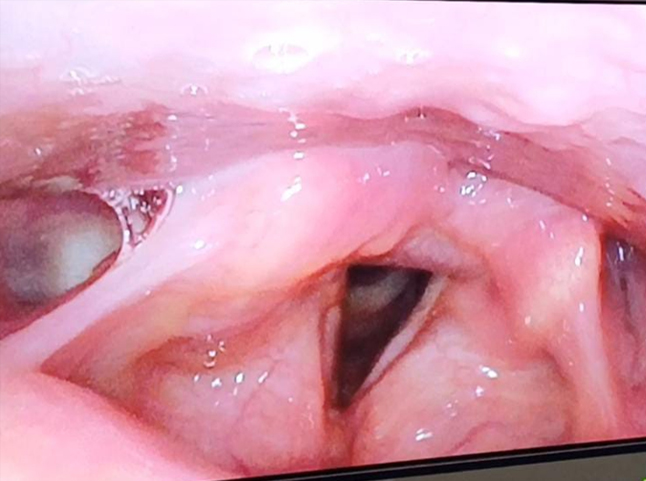

Physical examination revealed no cervical lymphadenopathy or palpable masses. Video laryngoscopy identified multiple yellowish polypoidal lesions involving the right vestibular band, posterior one-third of the right vocal cord, and anterior two-thirds of the left vocal cord. The lesions appeared firm, submucosal and non-ulcerative, with preserved bilateral vocal cord mobility (Figure1).

Figure 1. Videolaryngoscopic image showing yellowish polypoidal lesions involving right vestibular band and bilateral vocal cords

The patient’s post-operative recovery was uneventful. A significant improvement in her voice quality was noted at 4 weeks follow-up and she remains free of recurrence with satisfactory phonatory outcomes till date (Figure 5).

Figure 5. Follow-up videolaryngoscopic image done after 1 year showing no recurrence/residual lesion